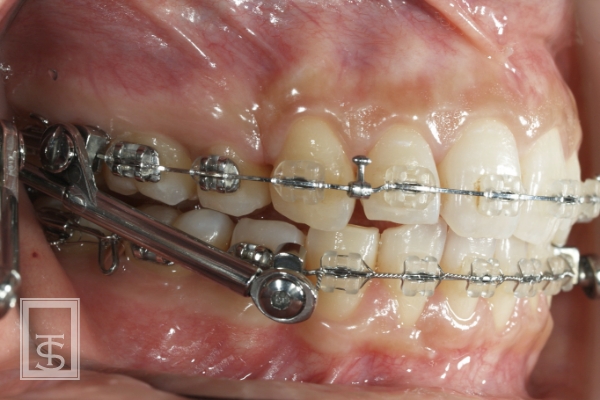

ハーブスト装置(Herbst appliance)

下顎骨成長促進、下顎骨前方誘導を行う装置となります。